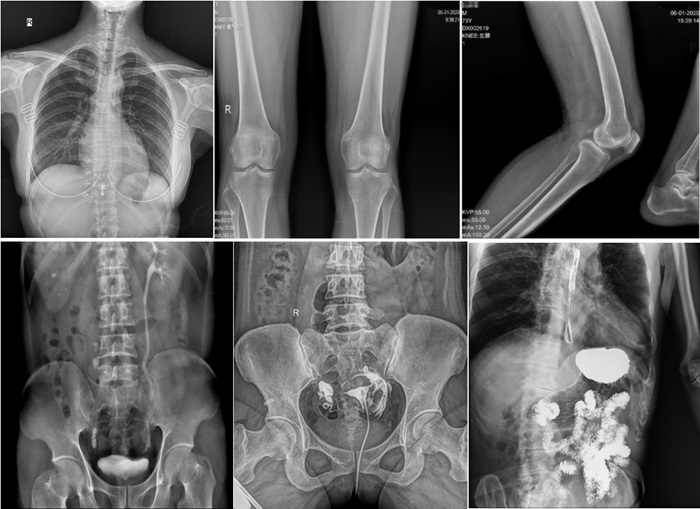

在實(shí)際應(yīng)用中,普利德動(dòng)態(tài)平板DRF展現(xiàn)出了多種優(yōu)勢(shì)。例如,在胸部影像檢查中,它清晰顯示肺部紋理和結(jié)節(jié),為肺癌早期篩查提供有力支持;在骨科領(lǐng)域,可用于骨折的診斷和復(fù)位效果評(píng)估,幫助醫(yī)生制定更精準(zhǔn)的治療方案;在消化系統(tǒng)檢查中,能有效發(fā)現(xiàn)胃腸道疾病的異常。

在婦科方面,不僅能夠直觀的觀察子宮形態(tài)、大小,輸卵管各部有無(wú)扭曲、管腔粘連以及梗塞情況,還可以在加壓推注下,使部分輸卵管輕、中度堵塞的患者得以通暢,起到有效的治療作用。